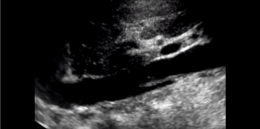

A free floating DVT is a deep vein thrombosis that is noted to be mobile during the ultrasound scan. Here is a video of a free floating DVT:

As acute DVT are not always adherent to the vein wall risk of embolization is greatest at that time. Free floating deep vein thrombi are visibly not adherent and often flap as blood flows across them.